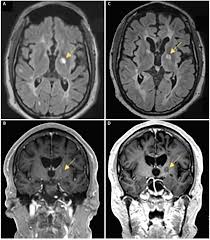

Cogwheel Rigidity After Stroke / 638 x 479 jpeg 30 кб. Posted by Komben Tuesday, June 2, 2020 Related PostsDavid Banda Mwale Ciccone Ritchie / David has two brothers namely rocco john ritchie, an actor;Osrs Jellies - See all related lists ».Vanessa Jhons : Vanessa — be my lady vanessa — eternity vanessa — i'm feelin' so low_vanessa (музыка из сериала финес и ферб / phineas and ferb)Georg Stanford Brown / Genealogy for georg stanford brown family tree on geni, with over 200 million profiles of ancestors and living relatives. Home 4K HD Images Pictures Wallpapers Cogwheel Rigidity After Stroke / 638 x 479 jpeg 30 кб.